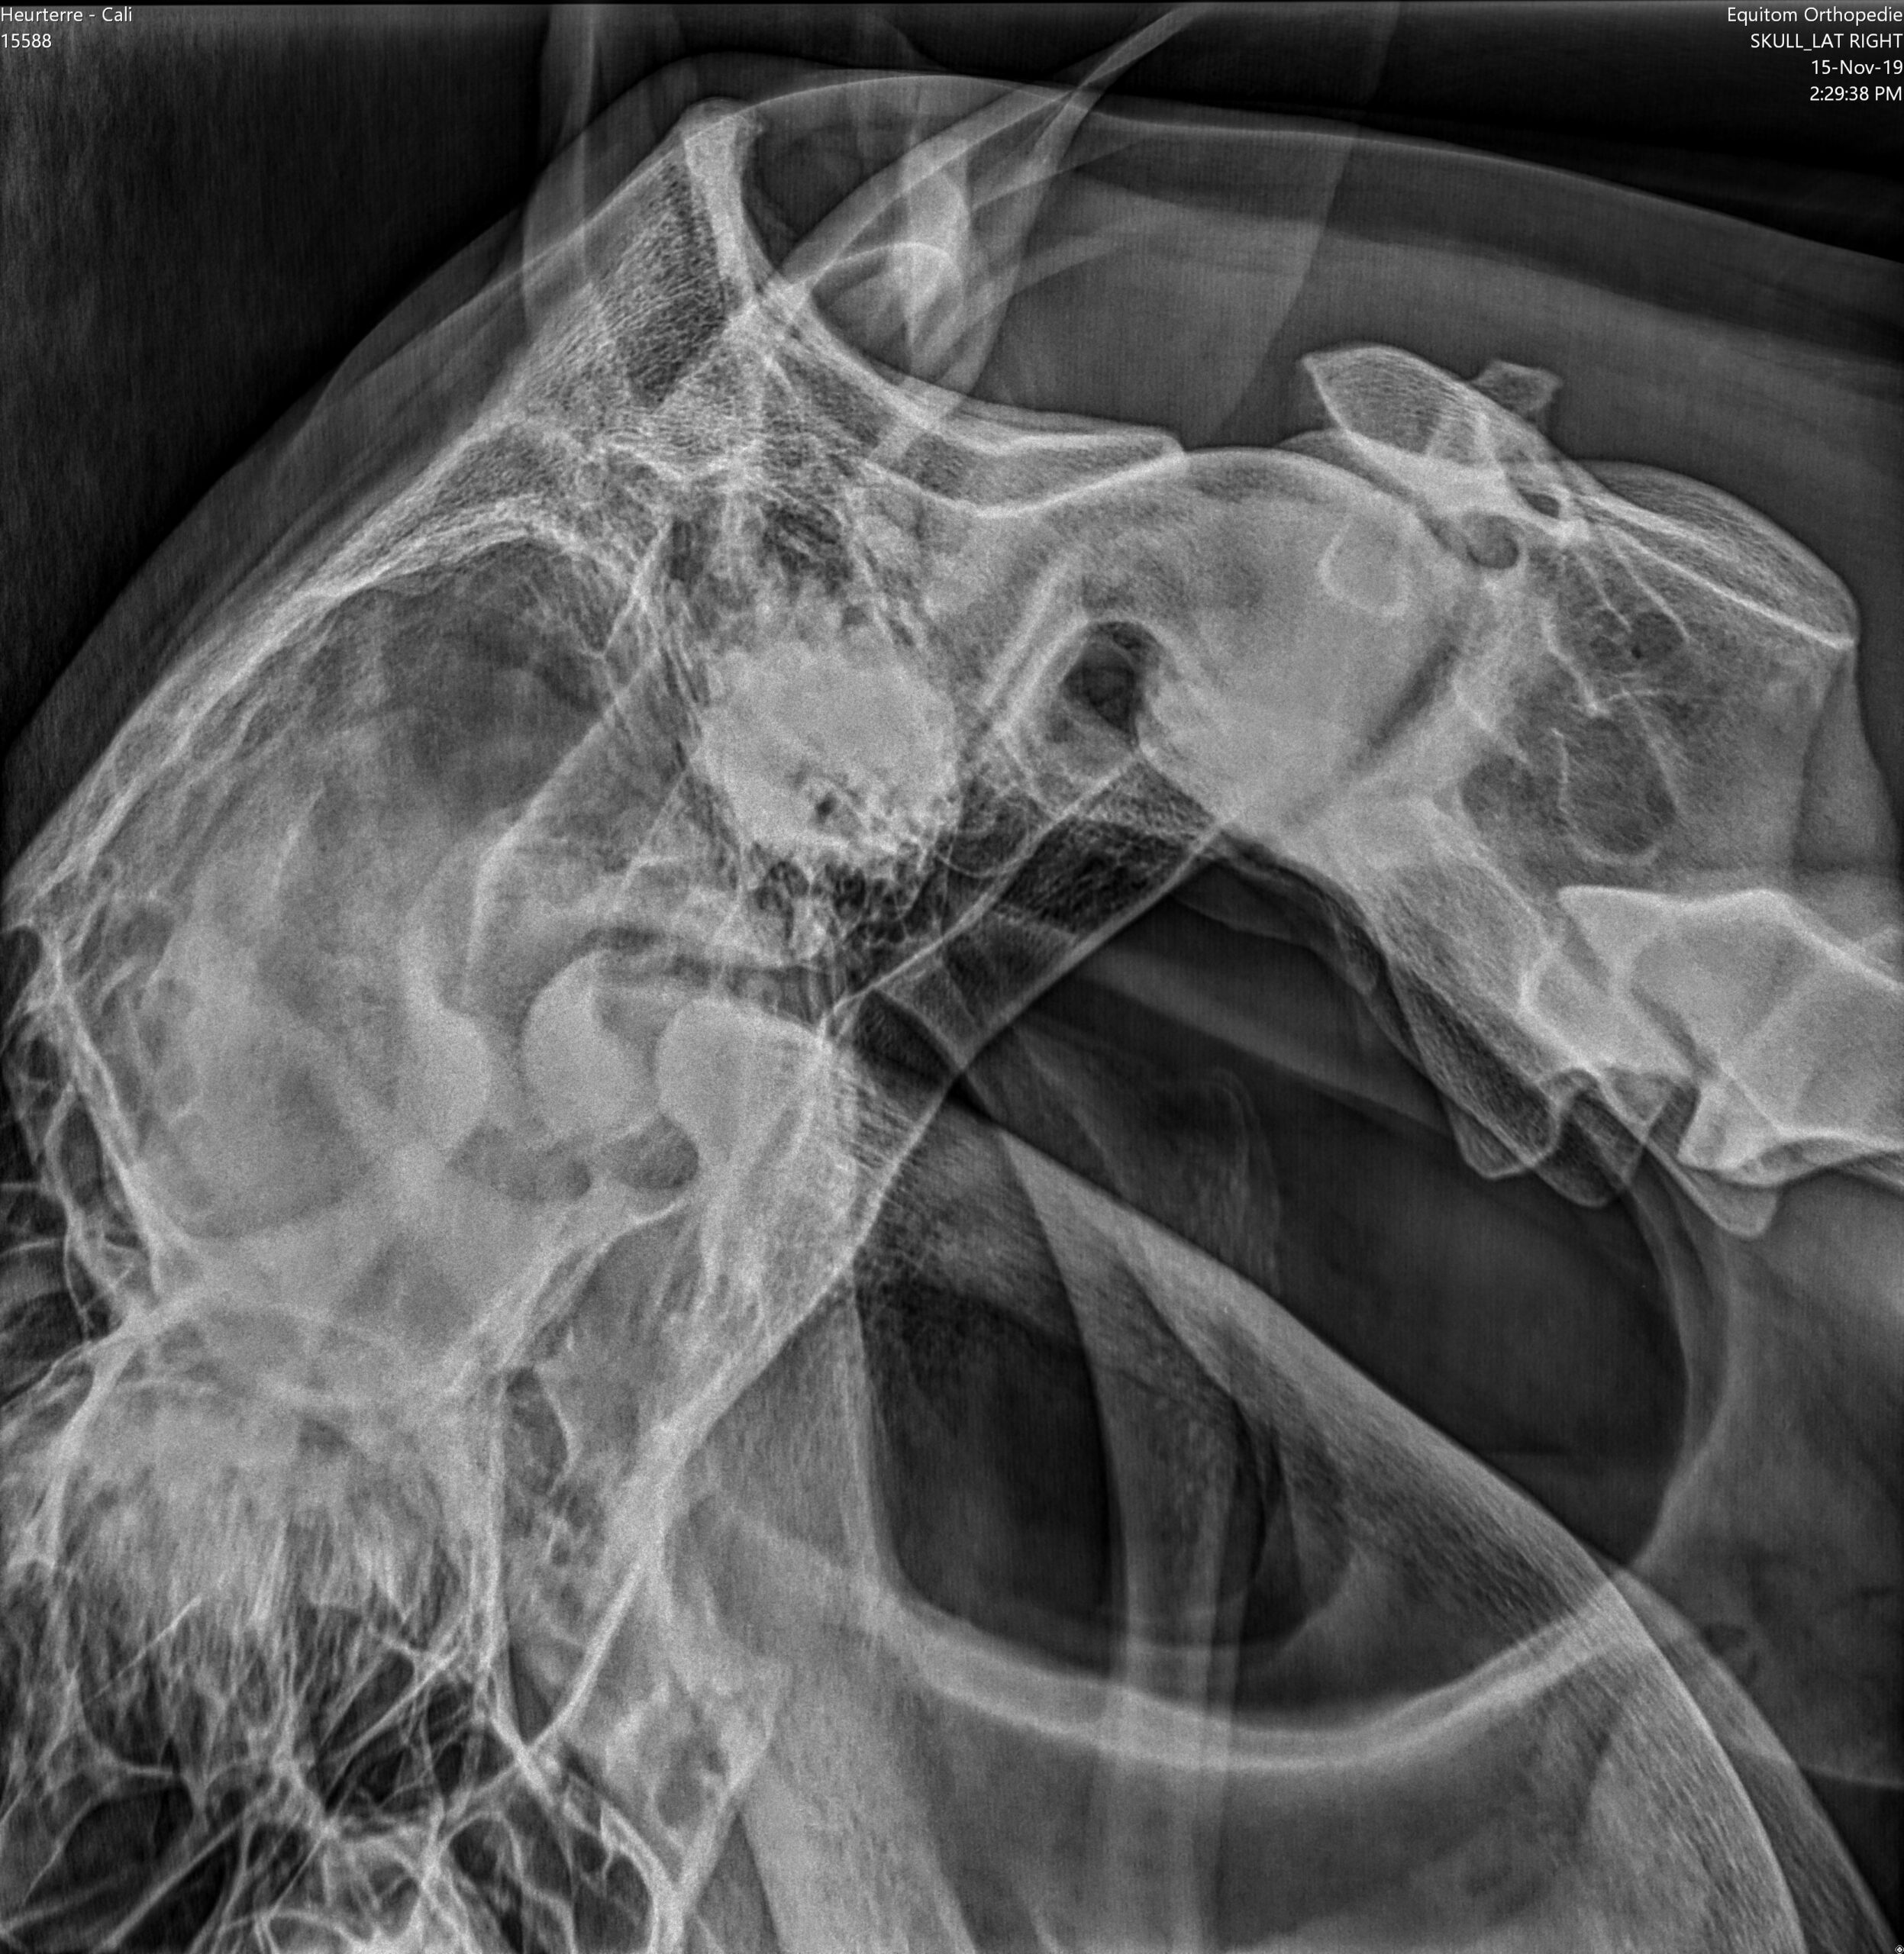

Každý kůň má dva vzdušné vaky, které leží po stranách hrdla. Jsou to pytlovité výchlipky Eustachovy trubice, která propojuje hrdlo a ucho koně. Vaky jsou naplněny vzduchem a jsou jasně viditelné na rentgenových snímcích jako tmavé plochy (obr. 1). Jejich funkce stále není zcela objasněná, ale je jisté, že kolem nich nebo přímo skrz ně vedou velmi důležité struktury.

Některé z hlavních cév zásobujících hlavu se nacházejí v těsné blízkosti stěn vzdušných vaků. Jedná se zejména o hlavní tepnu (krkavici), která vystupuje přímo ze srdce a zásobuje kyslíkem hlavu a mozek. Na úrovni hlavy se tato tepna rozdělí do několika silných tepenných větví, které procházejí stěnami vzdušných vaků (vnější a vnitřní větev krkavice a čelistní tepna, obr. 2).